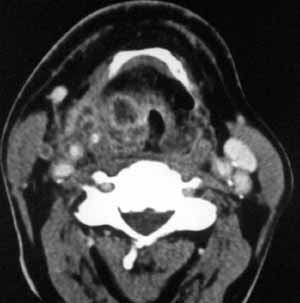

Рис. 1. КТА сосудов шеи у больного раком гортани. Метастатически увеличенные лимфоузлы в области бифуркации общей сонной артерии с компрессией внутренней яремной вены. Расширение поверхностной яремной вены, осуществляющей коллатеральный кровоток.